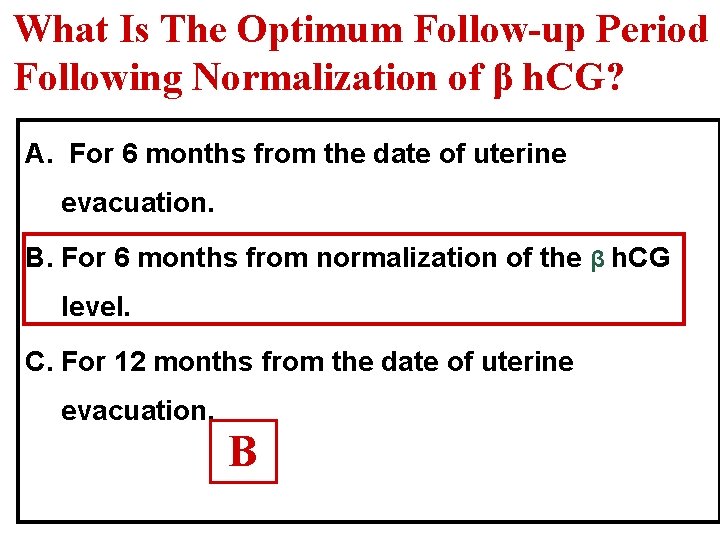

What Is The Optimum Follow-up Period Following Normalization of β h. CG? A. For 6 months from the date of uterine evacuation. B. For 6 months from normalization of the β h. CG level. C. For 12 months from the date of uterine evacuation. B

What Is The Optimum Follow-up Period After Which Pregnancy Is Allowed? It depends upon when h. CG has reverted to normal Ø ≤ 56 days of the pregnancy event: Follow up is 6 months from the date of uterine evacuation. Ø >56 days of the pregnancy event : Follow up is 6 months from normalization of the h. CG level. RCOG Guideline No. 38 ; 2010 At this period levels of βh. CG are monitored every month Practically once βh. CG has normalized after molar evacuation, the possibility of GTN developing is very low.